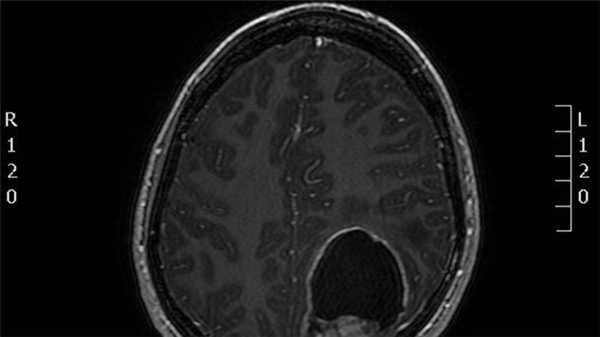

(а) МРТ, FLAIR, аксиальный срез: у мужчины 49 лет с головными болями в подзатылочной области в области IV желудочка определяется слегка гиперинтенсивное объемное образование, имеющее дольчатую структуру. Отмечается антеролатеральное распространение образования по направлению через левое отверстие Люшка в цистерну левого мостомозжечкового угла.

(б) МРТ, постконтрастное Т1-ВИ, аксиальный срез: у того же пациента определяется интенсивное, но слегка гетерогенное контрастирование объемного образования. При операции была диагностирована таницитарная эпендимома II степени злокачественности по классификации ВОЗ (grade II).г) Патология: